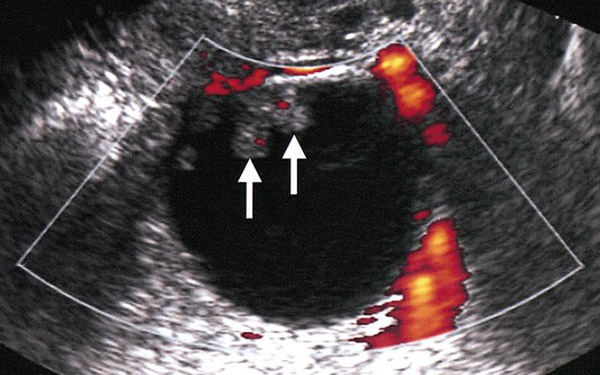

«Ηρθε σε εμάς λόγω υπογονιμότητας. Προσπαθούσε σχεδόν πέντε χρόνια να μείνει έγκυος. Η πρώτη μας κίνηση ήταν να την εξετάσουμε. Διαπιστώσαμε κατά την εξέταση ότι κάποιοι δείκτες ήταν ανεβασμένοι. Προχωρήσαμε σε λαπαροσκόπηση και εντοπίσαμε τους όγκους. Στείλαμε δείγμα για ταχεία βιοψία και διαπιστώθηκε καρκίνος ωοθηκών οριακής κακοήθειας» λέει στο kathimerini.gr ο κ. Καπετανάκης.

Πρόκειται για μία λιγότερο επιθετική μορφή καρκίνου . Οι οριακοί όγκοι των ωοθηκών είναι χαμηλής κακοήθεις όγκοι και αντιπροσωπεύουν το 10% -20% όλων των επιθηλιακών κακοηθειών όγκων των ωοθηκών. Η επίπτωσή τους είναι χαμηλή και υπολογίζεται σε περίπου 1,5-2,5 / 100,000 νέες περιπτώσεις ετησίως ενώ στο 20% αυτών ανευρίσκονται και τις δυο ωοθήκες. Στο ένα τρίτο των περιπτώσεων διαγιγνώσκονται πριν από την ηλικία των 40 ετών.

Επειδή οι ασθενείς με αυτόν τον τύπο όγκου είναι νεότερες κατά τη στιγμή της διάγνωσης η διατήρηση της γονιμότητας αποτελεί σημαντικό παράγοντα στο σχεδιασμό της θεραπείας. Εκεί λοιπόν εστίασε ο κ. Καπετανάκης και η ομάδα του, καθώς, δεν προχώρησαν σε απευθείας αφαίρεση ωοθηκών αλλά η ασθενής υποβλήθηκε σε λαπαροσκοπική αμφοτερόπλευρη αποφλοίωση ωοθηκών οπού έγινε λεπτομερείς αφαίρεση όλων των επιφανειακών, εξωφυτικών όγκων που ήταν ορατοί μέχρι να αναδειχθούν τα υγιή όρια των ωοθηκών και συγχρόνως πάρθηκαν πολλαπλές βιοψίες περιτοναίου και έγινε μερική επιπλεκτομή.